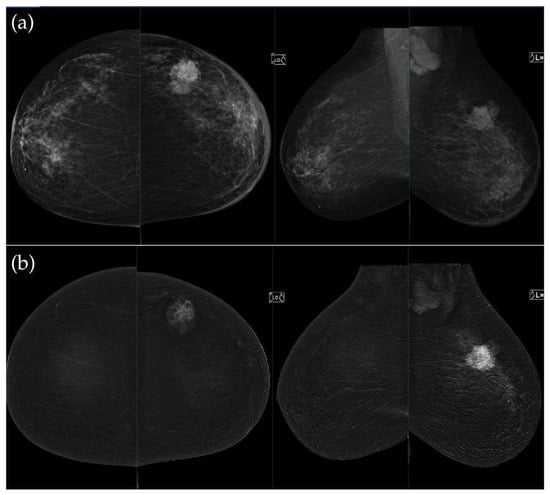

Figure 3. (a) Standard craniocaudal (CC) and mediolateral oblique (MLO) low-energy views reveal an irregular, spiculated mass of the left breast. The right breast shows a histopathologically confirmed fibroadenoma with dystrophic calcifications. (b) Recombined contrast-enhanced images (CC and MLO views) demonstrate early, complete heterogeneous enhancement. No pathologically enhancing axillary lymph nodes are detected. Histopathological analysis confirmed Luminal A breast carcinoma.

Figure 4. (a) Standard CC and MLO low-energy views reveal an irregular, spiculated mass with associated retraction of Cooper’s ligaments in the upper outer quadrant of the left breast. No suspicious microcalcifications are seen. The right breast appears unremarkable. (b) Recombined contrast-enhanced images (CC and MLO views) demonstrate an irregular, non-circumscribed lesion in the upper outer quadrant of the left breast with rapid early heterogeneous enhancement. Partially visualized axillary conglomerate on the left also demonstrates heterogeneous contrast enhancement in the early phase. Contralateral axilla is unremarkable. Histopathological analysis confirmed a Luminal B breast carcinoma.